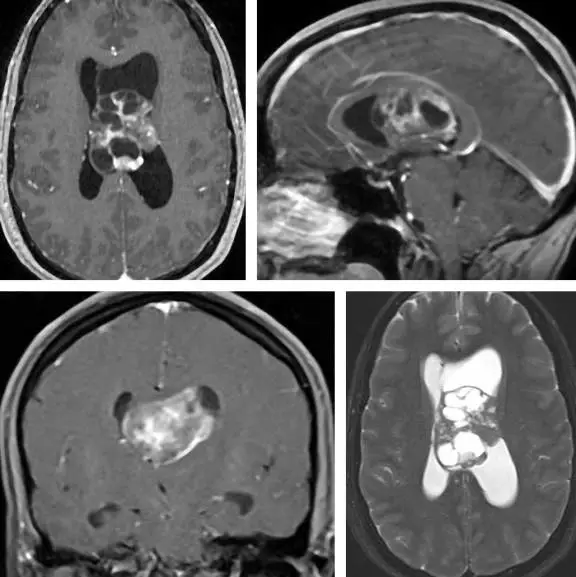

图2. 示一例中线巨大侧脑室神经细胞瘤(起源于透明隔)。笔者从左侧经胼胝体入路进入肿瘤,但因同侧扣带回遮挡视野以及肿瘤粘附于此处脑室壁无法充分暴露,未能完全切除肿瘤。因此也许选择顺应肿瘤长轴的右侧经顶下沟皮层入路更合适。